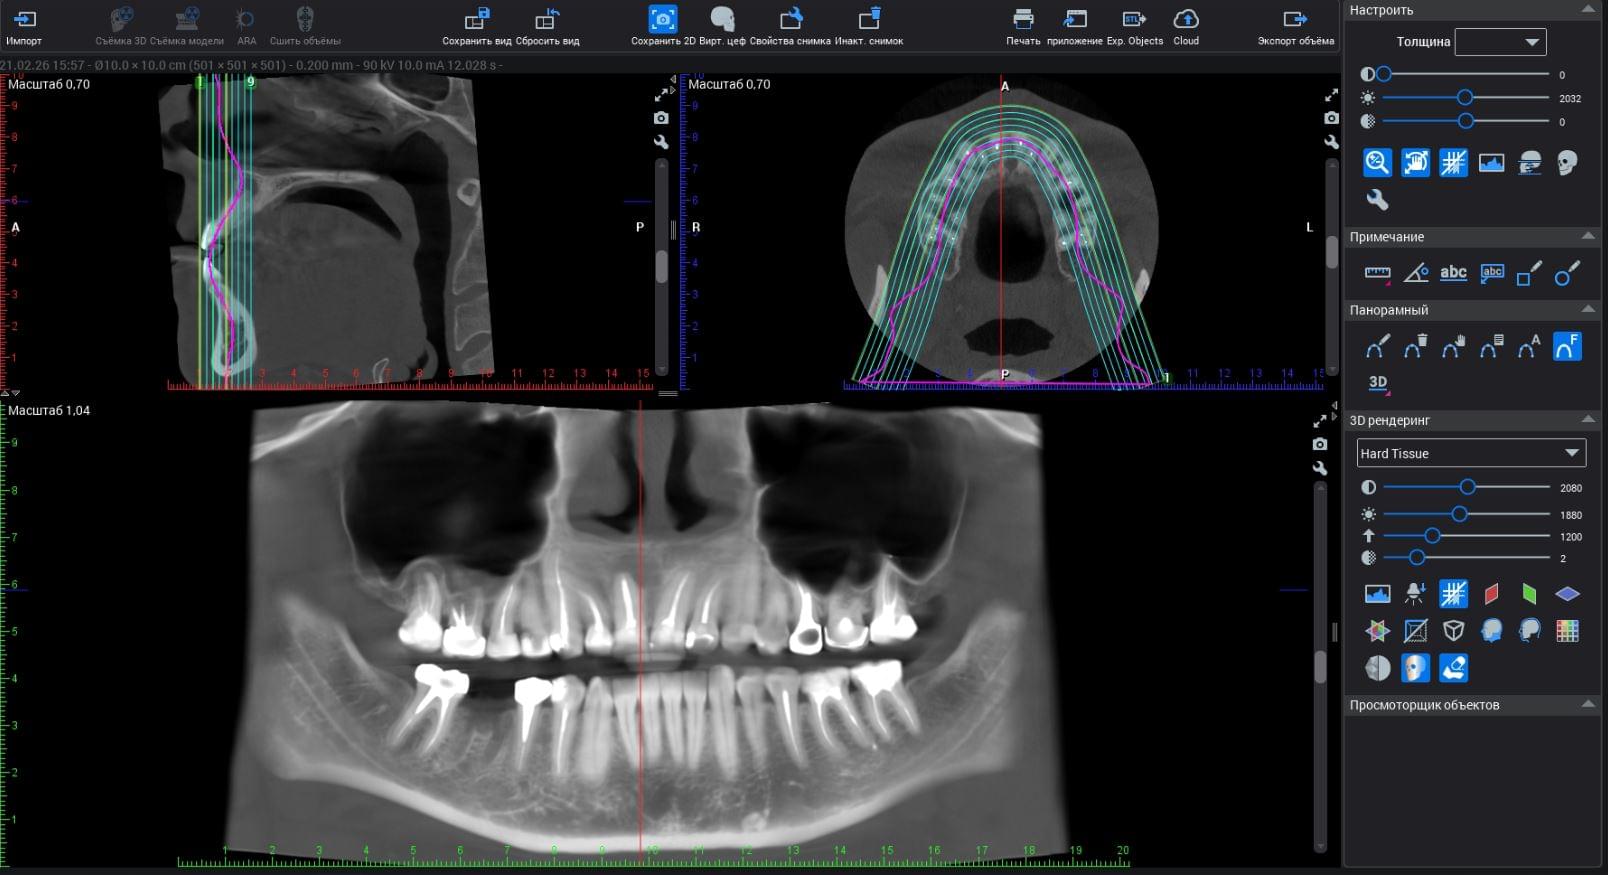

Чому звичайного рентгену недостатньо? Прихована реальність за межами 2D

Чому сучасна стоматологія відмовляється від плоских знімків на користь 3D-діагностики. На реальних кейсах MyRayLab ви дізнаєтесь:

Головний недолік 2D-рентгену — це площинне зображення. Зуби, корені, щільна кістка та гайморові пазухи накладаються один на одного, створюючи «візуальний шум».

Візуальне порівняння (Кейс одного пацієнта)